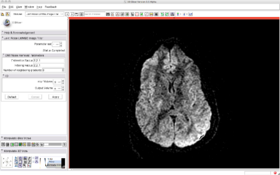

The following screenshots illustrate how to use the filter and the expected results (note that the optimal parameters strongly depends on the characteristics of the image: voxel size, number of gradients...).

Before filtering:

After filtering: